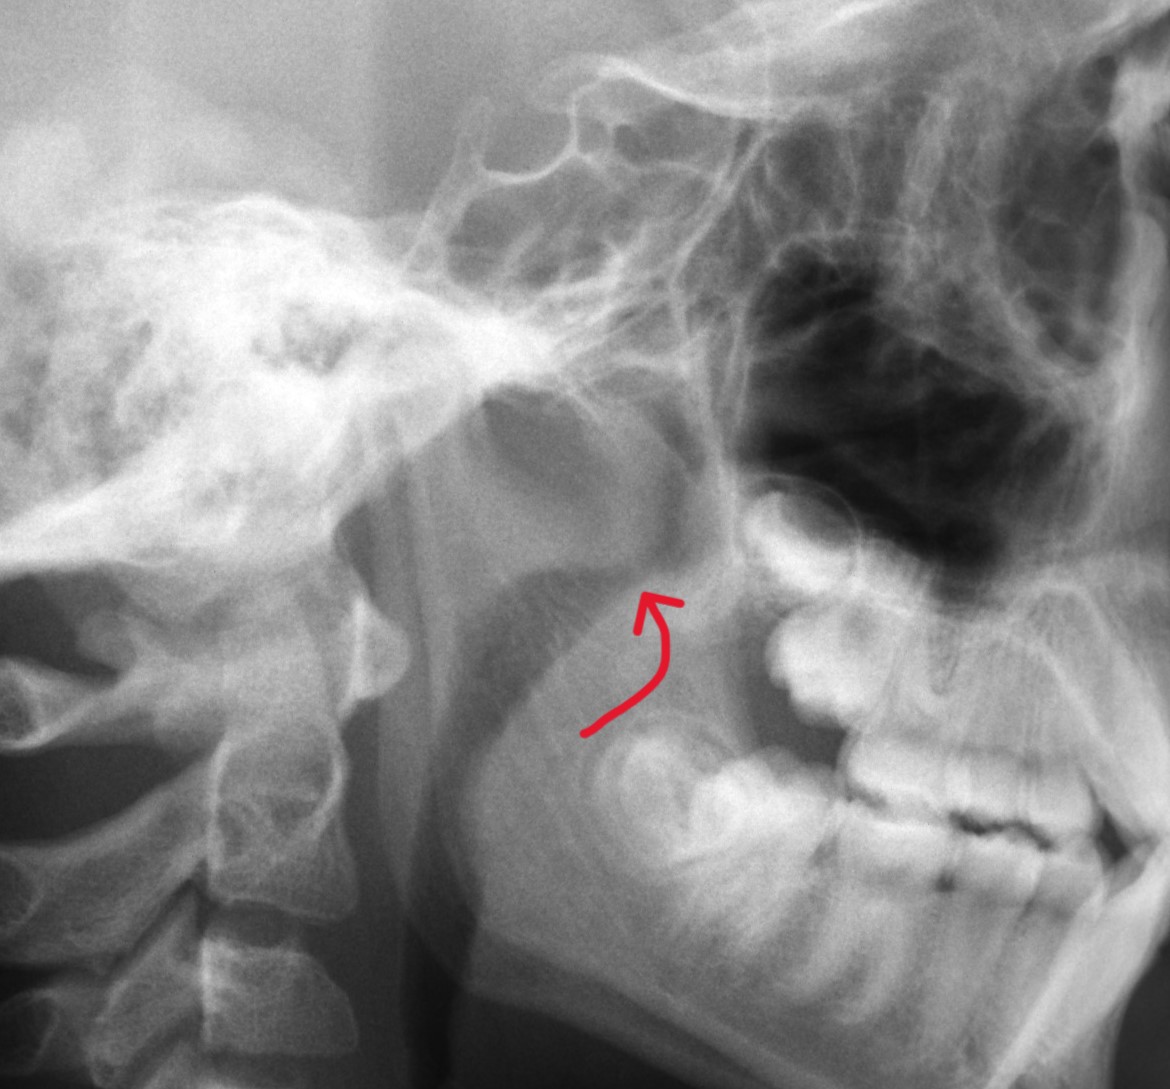

Through the ceph above, we can see that this patient still has some growth spurts to look forward to, but not only does this particular ceph show the patient's growth, we can also see their airway. A huge benefit of cephs is the ability to see a patient's adenoids and their relation to a patient's airway, as seen in the image to the right.

Have you noticed your child tends to breathe through their mouth or snore at night? They could have enlarged adenoids, which can impact their ability to breath properly through the nose. A benefit of an ortho consult, especially at an early age, is catching these breathing and adenoid issues early on, allowing for early intervention with your child's PCP and an easier recovery period if surgery is required.